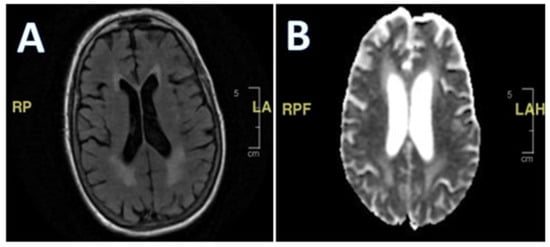

Her second hospital admission was precipitated by repeated ground-level falls from severe bilateral leg weakness. On this occasion, she described worsening back pain with ambulation. She also developed a left facial droop during the second admission. Extensive imaging, including another MRI and CT scan, showed no ischemic changes in the head and neck or acute stroke. Repeat cerebral MRI with and without contrast was negative (Figure 2). Lumbar spine MRI showed advanced degenerative disk disease but no significant pathology explaining her bilateral lower-extremity weakness (Figure 3). Lumbar spine CT showed moderate spinal stenosis at the two lowest vertebrae of the lumbar spine and a 2 mm anterolisthesis. The patient did not exhibit urinary or fecal incontinence.

Figure 2. (A,B) MRI of brain with and without contrast. White matter disease and volume loss indicating chronic microangiopathic changes. No abnormal parenchymal mass or extra-axial collection identified.